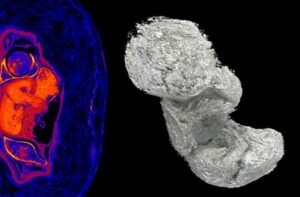

Nonostante il nome maschile trovato sul sarcofago, i ricercatori – durante una prima indagine, anch’essa non invasiva – avevano riscontrato la mancanza dell’organo maschile che, normalmente, veniva mummificato con il resto del corpo. Ulteriori indagini, svolte con la Tac e con i più avanzati strumenti di diagnostica avevano permesso di svolgere virtualmente le bende e di scoprire il corpo di una giovane donna. Altre ricerche hanno consentito di vedere il corpo del bambino e di conoscere le sostanze che furono utilizzate per la mummificazione.

La Tac, attraverso la misurazione del feto – ha consentito di stabilire che la donna era incinta da 28 settimane e pertanto era entrata nel settimo mese di gravidanza. Il settimo mese di gravidanza è infatti compreso tra le 26 settimane+3 giorni e le 30 settimane+4 giorni.

All’interno del corpo della giovane donna, il passaggio da ambiente alcalino ad ambiente acido ha causato la lisciviazione di minerali dalle ossa fetali, che hanno cominciato a disseccarsi e mineralizzarsi.